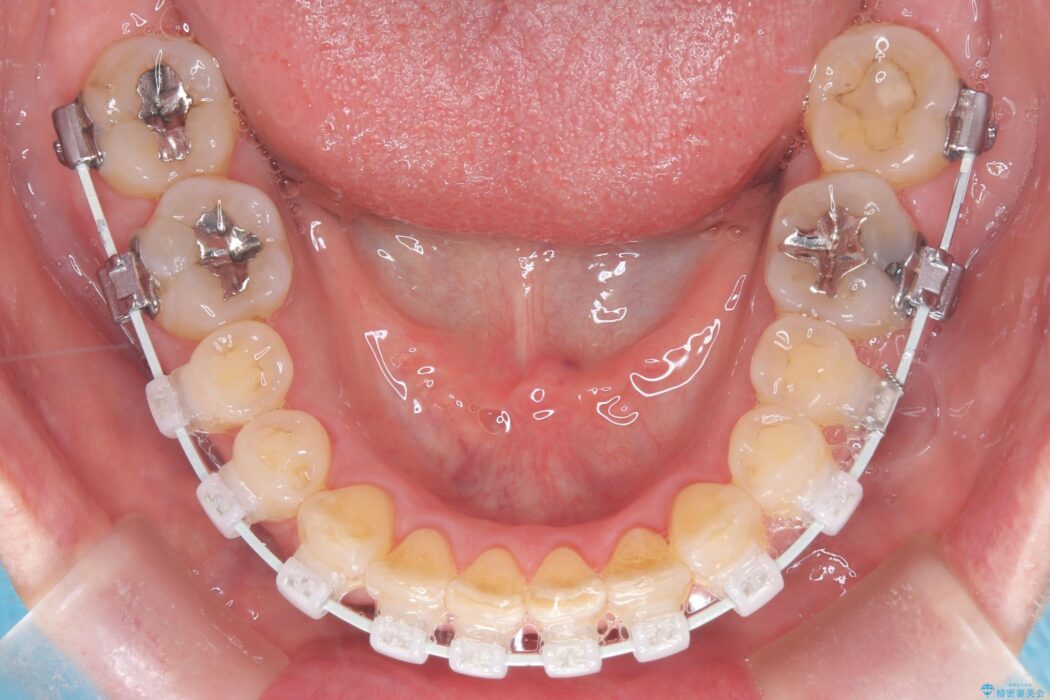

今回の矯正治療では、歯の色に近い目立たない審美ブラケットとワイヤーを使用しました。

ワイヤー矯正ならではの確実な歯のコントロールにより、当初の計画通り約1年という短い期間で、前歯のガタつきが解消。見た目が美しく整っただけでなく、清掃しやすい機能的な歯並びを獲得していただけました。